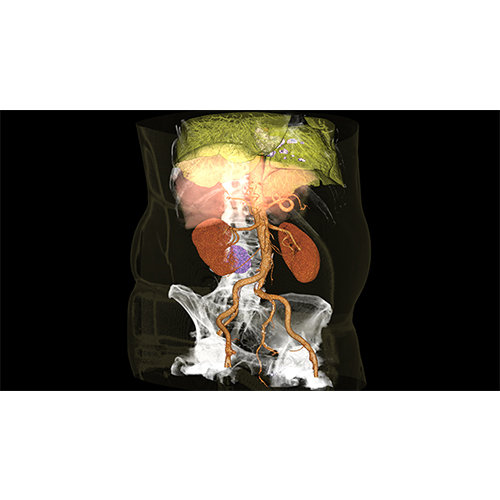

ANYTHINK 经导管主动脉瓣膜置换术分析系统